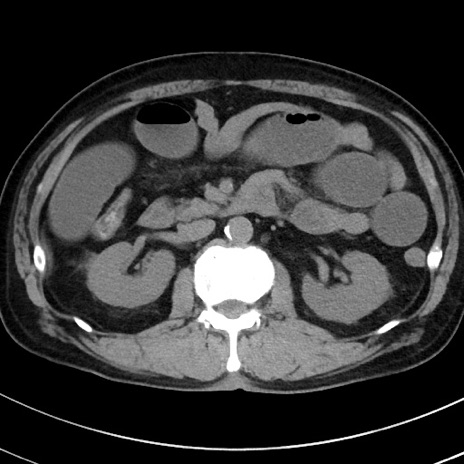

冠状断像

【症例】70歳代 男性

【主訴】腹痛・嘔吐

【現病歴】昨晩より、嘔吐・腹痛あり。今朝になっても嘔吐あり。来院。

【既往歴】心臓バイパス手術、開腹胆摘、腸閉塞

【身体所見】BP 107/71mmHg、HR 116/min、腹部:平坦、軟、下腹部に軽度圧痛あり。反跳痛なし。

【データ】WBC 15100、CRP 0.32